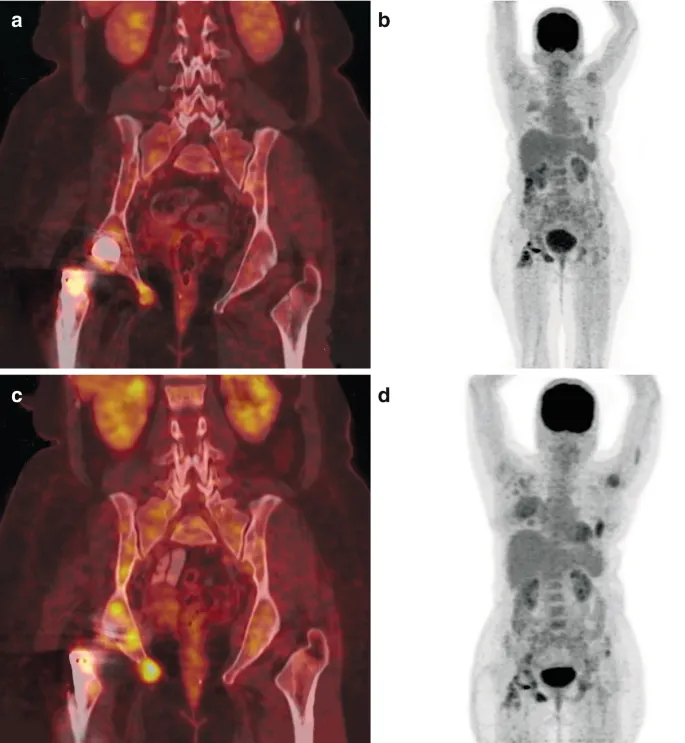

| F-18 FDG PET/CT | ↑ glucose use (inflam. cells/microbes via GLUT). | FUO, osteomyelitis (spinal), vasculitis, sarcoidosis, therapy monitor. | Rapid (~1h), high resolution. | Non-specific (tumors, post-op), glucose control, physiological uptake (brain, heart, GU). |

- $^{18}$F-FDG PET/CT: Key modality; detects inflammation, infection, malignancy. High sens.

- $^{18}$F-FDG PET/CT: Differentiates OM vs. Charcot foot. High acc.

- Vasculitis (Large Vessel): $^{18}$F-FDG PET/CT for activity & extent (e.g., Takayasu).

- IBD: $^{18}$F-FDG PET/CT for activity assessment, extent.

- FDG-PET/CT is widely used, showing ↑ glucose uptake in inflammatory cells like macrophages and neutrophils.

- FDG-PET/CT is also crucial for Fever of Unknown Origin (FUO), vasculitis, and IBD.